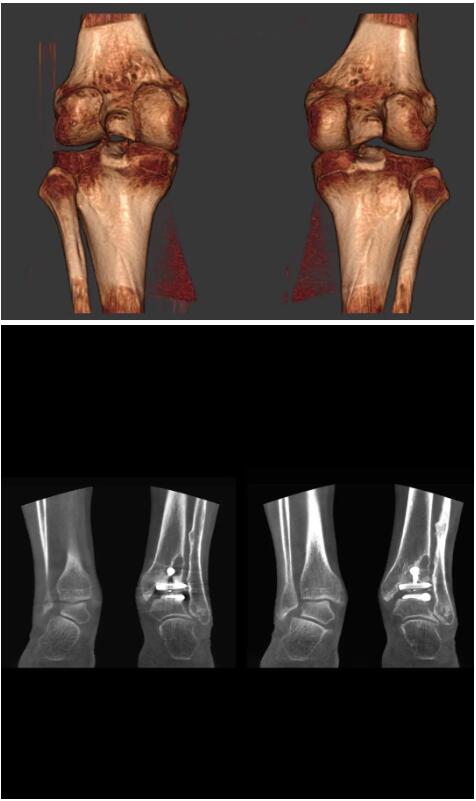

另外一款被稱為世界上最小的CT,它的重量僅300磅,不僅能夠掃查足部,還可以檢查膝蓋和上肢等。

與上面介紹的CT一樣,它同樣具有輻射低、占地空間?。?3*36)的特點,隨開隨用(支持直接接入墻上的插座)。

這款CT使用非常方便,通過上下移動保持與患者的手臂或者雙腿齊平,掃描快速,僅需要30秒左右就可以完成掃查。

以上介紹的CT均來自國外同一家公司,這些CT均配置了可視化軟件,可以進行切片、3D重建以及大型CT附帶的所有典型的操作功能。

以下是這些“特立獨行”的CT所拍出來的圖像: